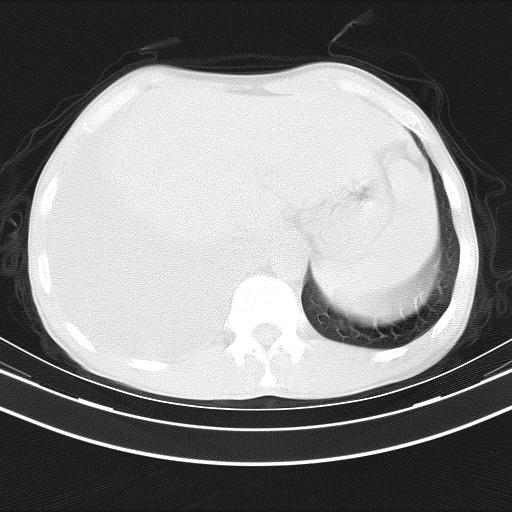

男性,44岁,结核病史多年。现胸闷气短,咳嗽,偶咳血。

右侧胸腔积液

右肺下叶不张

双肺多发结节影最分空洞形成考虑占位不除外结核

双肺陈旧性病变

1、右侧大量胸腔积液伴右肺压缩性膨胀不全,建议抽液治疗后复查 2、两肺继发性tb伴空洞形成。

1)两肺继发性肺结核伴空洞形成,左肺多发性结核球。2)右侧大量胸腔积液伴右肺部分膨胀不全。3)纵隔淋巴结肿大。

吉大一院胸水抽检结果:结核性胸水